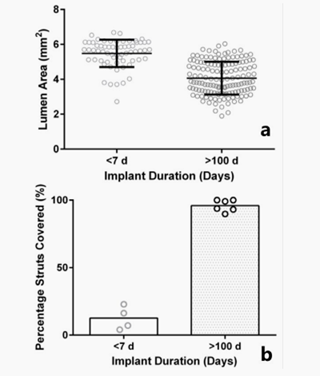

Opie等人使用显微ct和组织学技术评估了12只在上矢状窦植入支架190天的动物的新生内膜增生。植入两周后,支架部分在血管壁中的比例明显增加。从第2周到第4周,组织学结果从前两周的5.43±2.2%增加到87.8±2.0%。显微ct观察显示,支架到管腔的距离从植入后2-4周时的570±33 μm减少到4-8周时的367±10 μm,此后支架管腔厚度稳定。图9显示了长期电极植入前后血管内管腔面积的变化和支架融入血管壁的比例。

图9 (a)植入前7天和植入后100天管腔面积的变化

(b)植入前7天和植入后100天支架融入血管壁的比例的变化